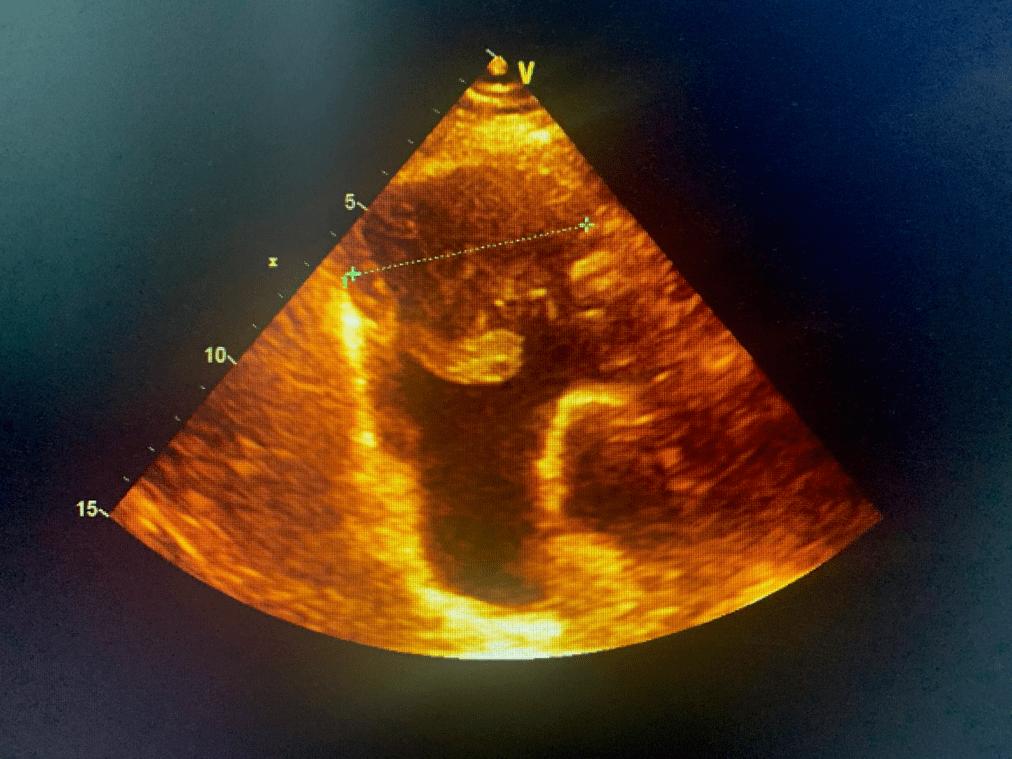

【读片】心脏肿瘤——心包间皮瘤,伴大量心包积液,难得一见!